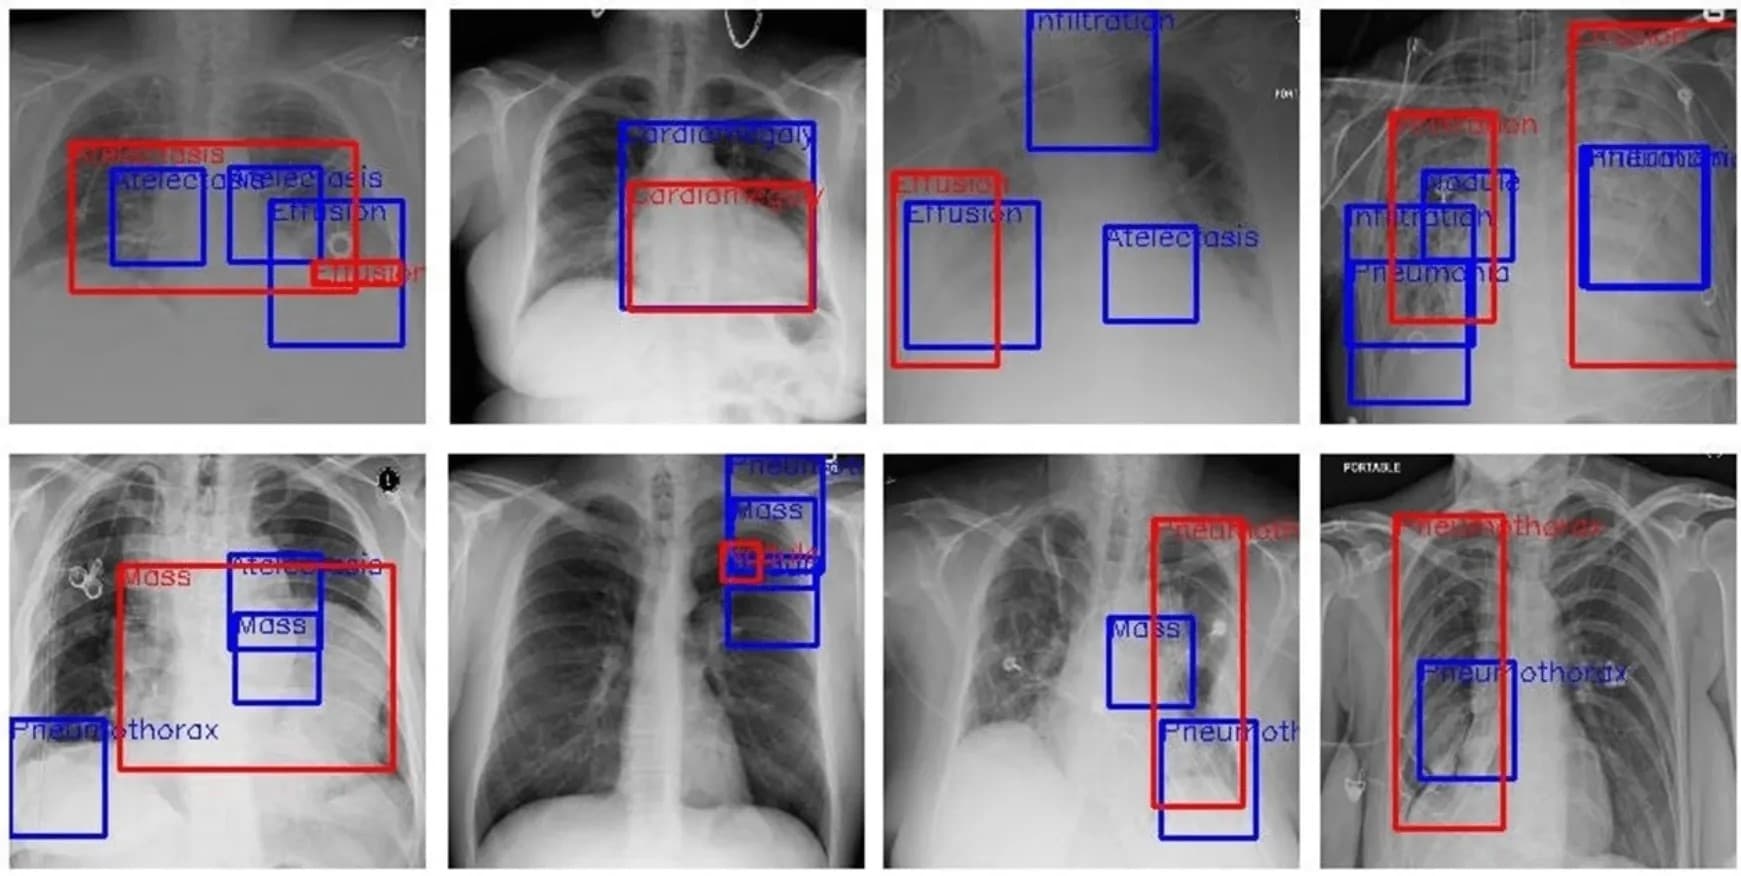

Medical Data Annotation

Precise medical data annotation for diagnostic AI, specializing in DICOM, imaging, and clinical text.